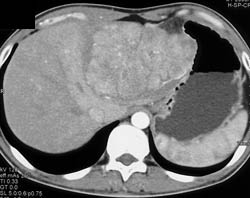

Hepatoma